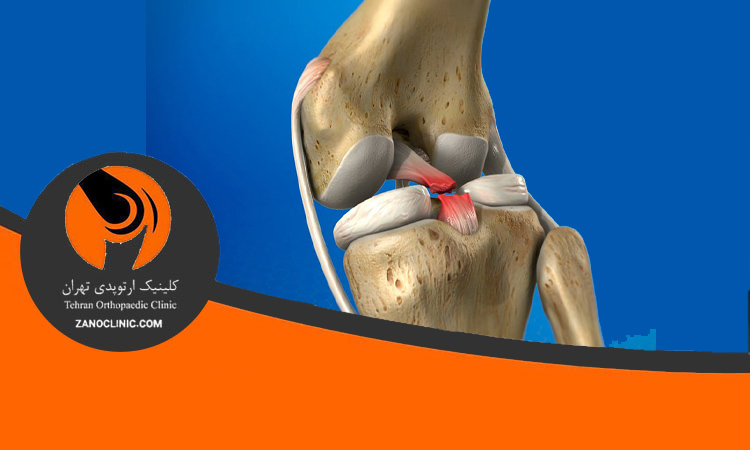

ترمیم رباط صلیبی

ترمیم مینسک و رباط صلیبی PCL و درمان اولیه آن

کلینیک ارتوپدی زانو کلینیک با ارائه انواع خدمات جراحی زانو اعم از تعویض مفصل زانو و لگن، بازسازی مینسک و رباط صلیبی PC، جراحی غیر تهاجمی ACL به صورت آرتروسکوپیک و … با جدید ترین متدهای دنیا و پیشرفته ترین تجهیزات پزشکی، در حال خدمت به شما عزیزان می باشد.